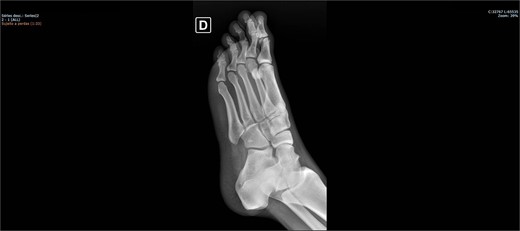

On physical examination, there was pain upon palpation over the dorso-lateral region of the midfoot, mild edema, hyperemia, inability to walk, and restricted ankle extension. Based on the physical examination, radiographs were requested. The examinations (Figs 1 and 2) showed inferomedial displacement of the cuboid bone without the presence of a fracture, diagnosing an isolated cuboid dislocation. He was immobilized and admitted for an open surgical reduction procedure.